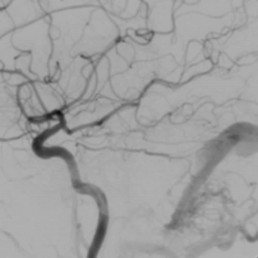

Whilst MRI scans provide a lot of information about the status of the brain, the definitive diagnosis of a dural fistula is made by cerebral angiography.

The treatment options are best discussed with the imaging and diagnostic cerebral angiogram, but include:

- Endovascular embolisation. Passing a fine catheter from the vessels at the top of the leg up to the region of the fistula in the brain. Fine platinum coils, glue or other embolic agents are used to block up the abnormal connections.